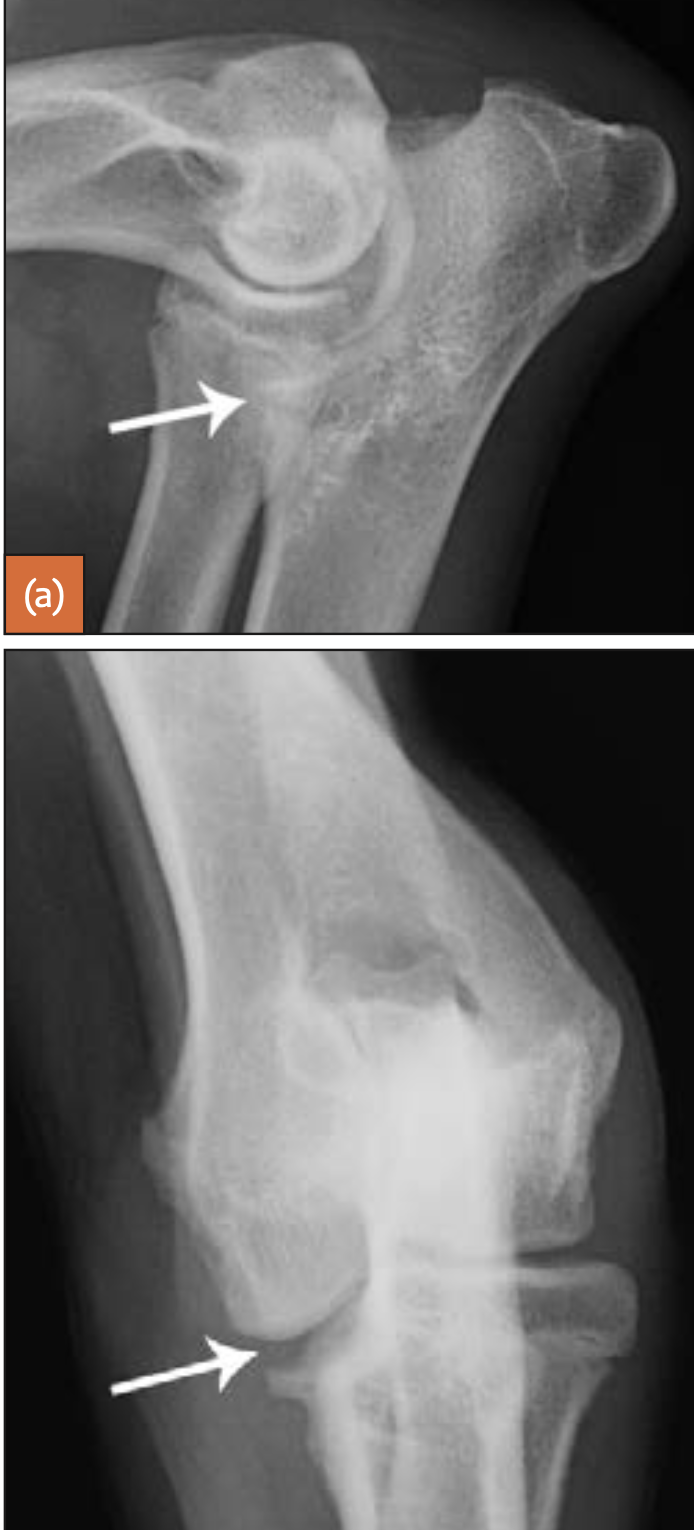

43

4-year-old Rottweiler

large separate medial coronoid fragment superimposed on the cranial radius (arrowed). Osteophytic reactions are seen on the cranial margins of the joint and on the anconeal process and subtrochlear sclerosis.